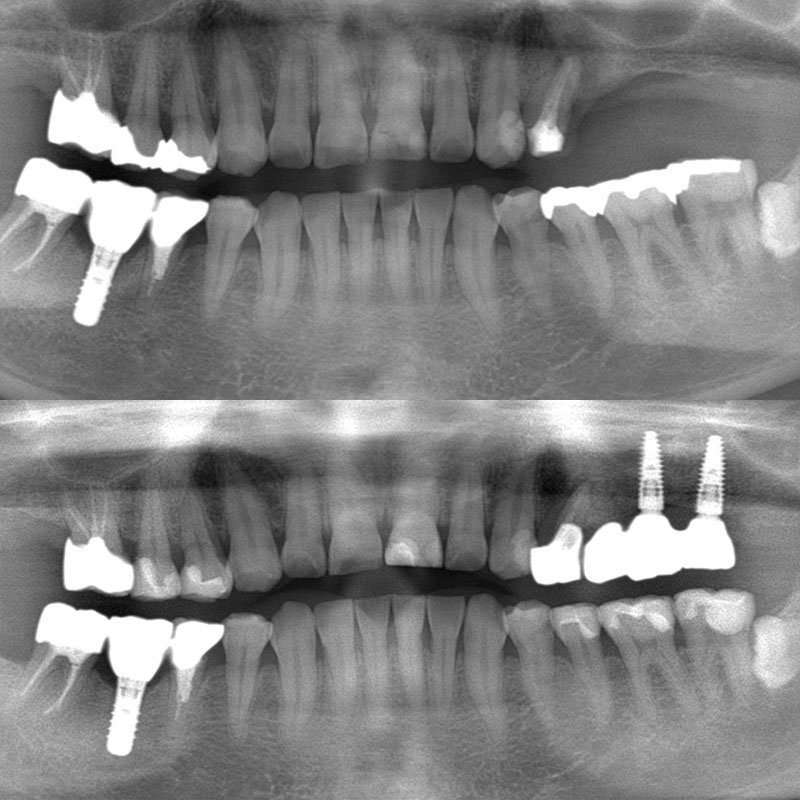

臼歯のインプラント

「抜歯した奥歯にインプラントを入れたい」とご相談いただきました。

過去に歯根破折(歯の根が折れたり欠けたりひび割れたりすること)が原因で、他院で左上の奥歯を抜歯され、当院へはインプラント治療をご希望されてご来院いただいた患者様です。

拝見したところ、左上の奥歯が抜歯後そのままの状態でした。

食いしばりがとても強く、その結果歯の根が折れてしまったようです。

患者様がインプラントをご希望だったため、ストローマン社製のインプラントを用いて奥歯を再建する治療をご案内し、スムーズに治療に進みました。

また今回の患者様は骨の量が少なかったため、骨造成術(サイナスリフト)を併用しています。

かみ合わせの異常はなく、現在もメンテナンスでご通院いただいています。

| 患者様 | 50代男性 |

|---|---|

| 主訴 | 抜歯した奥歯にインプラントを入れたい |

| 治療方法 | インプラント 骨造成術(サイナスリフト) |

| 治療費 | 1,177,000円(税込) |

| 治療期間 | 8ヶ月 |